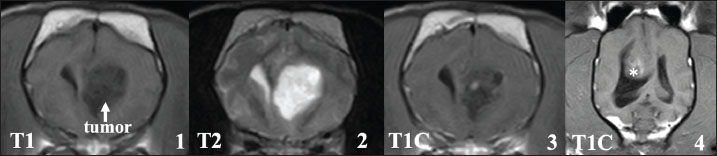

However, in 4 cases, the neurological signs recurred after a period of clinical stability, and the owners of these cases requested MRI re-evaluation when clinical symptoms recurred (cases A1–A4). The median duration between the end of radiotherapy and clinical worsening was 256 (range: 28-457) days. At the time of recurrence, all 4 cases exhibited ataxia, and 1 case could not stand unaided. In addition, epileptic seizures recurred in 2 of the 4 cases despite antiepileptic medical treatment. The MRI features of these cases are described in detail below. These cases then worsened, with death eventually resulting from the progression of neurological symptoms.

Magnetic resonance imaging of recurrent cases (A1–A4)

The MRI features of these recurring cases (A1–A4) are shown in Fig. 4. In all 4 cases, MRI showed that the primary tumor tissues had almost completely disappeared. However, in the contrast study, sagittal T1-weighted images of these 4 cases showed clear enhancement in the leptomeningeal region, which was most evident in the area spanning the ventral side of the brainstem to the cervical spinal cord (Fig.4,1-4). In addition to these leptomeningeal enhancements, two cases (A1 and A3) had space-occupying lesions in the cervical and/or thoracolumbar spinal cord along the central canal of the spinal cord (Fig.4,5-8). The signal intensities of both lesions were slightly low in T1-weighted images, and slightly high in T1-weighted and T2-weighted images, respectively. The spinal lesion showed only minor enhancement in one patient, but there was clear enhancement in the other. Furthermore, in case A3, multiple mass lesions were found in the thoracolumbar spinal cord (Figs. 4 and 7). Significant obstructive hydrocephalus was observed in one case (A4, Fig.4, 9-10). These findings are highly similar to those showing CSF drop metastasis, which was recently reported in dogs (Vigeral et al., 2018; Bentley et al., 2021).

Fig. 4. MRI findings of FB cases in which clinical symptoms recurred after radiotherapy (cases A1–A4, T1: T1-weighted image, T2: T2-weighted image, T1C: T1-weighted image with contrast medium). Upper lane (1–4): A clear enhancement was observed in the meninges around the brainstem (yellow arrows). Middle lane (5–7): Spinal lesions observed at clinical recurrence (green arrows). The lesion located in the central cervical spinal cord of case A3 showing high-signal intensity on T2-weighted image (5) showed no contrast enhancement (6, green arrow), whereas the leptomeningeal region showed clear enhancement (6, yellow arrows). Multiple lesions were also observed in the thoracolumbar spinal cord in this case (7). Lower lane (8–10): Cervical spinal lesions in patient A1. Unlike case A3, these lesions showed clear enhancement, similar to that of the leptomeningeal region (8, green arrows). In case A4, severe obstructive hydrocephalus was observed, with dilated lateral (9) and fourth (10) ventricles (orange arrows).

To investigate the causes of the shorter MST, we re-examined the MR images obtained at the recurrent phase in four cases (A1–A4). Contrast enhancement of the leptomeninges around the brainstem was observed in all 4 cases. In a report by Vigeral et al. (2018), similar MRI findings of ventral brainstem leptomeningeal enhancement were obtained after radiotherapy for oligodendroglioma in the English bulldog, and the investigators interpreted these data as indicative of CSF drop metastasis, using this term for the first time in small animal practice. CSF drop metastasis refers to tumor metastatic forms in which metastatic lesions are formed within the brain, and in some cases, within and/or around the spinal cord by tumor cells disseminated into the CSF. Nakamoto et al. (2018) reported similar MRI findings, suggestive of CSF drop metastasis, during follow-up of an oligodendroglioma in a single case of FB treated with radiotherapy. In the report, acceptable local control of the primary lesion was obtained before clinical symptom recurrence, as in our cases. In addition to leptomeningeal enhancement around the brainstem, lesions in the spinal cord and an obstructive hydrocephalus were concurrently observed at the recurrent phase in 2 cases and in one case, respectively. These MRI features have also been described in previous reports; in their cases, Vigeral et al. (2018) and Nakamoto et al. (2018) reported lesions in the spinal cord and significant hydrocephalus, respectively. The MRI findings in the present study were consistent with previously reported characteristics of CSF drop metastasis.